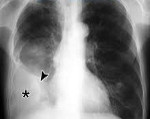

Для первичного выявления осумкованного плеврита чрезвычайно важны данные полипозиционой рентгенографии грудной клетки (в прямой, боковых и косых проекциях) и рентгеноскопии легких. Рентгенологически осумкование проявляется в виде затемнения характерной локализации и формы. В сложных случаях для дифференциальной диагностики требуется наложении искусственного пневмоторакса и пневмоперитонеума, проведение КТ легких. Длительное существование осумкованного плеврита может отразиться на состоянии легочной паренхимы. Поэтому для оценки изменений прилежащих отделов легкого (бронхов, сосудов) используются рентгеноконтрастные исследования - бронхография и ангиопульмонография.